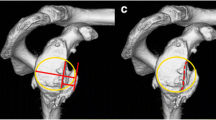

The assessment of the osteophyte was performed in T1-weighted MRI sequences in the coronal plane with the biceps anchor in the most prominent position (Fig. 1, P1, P4). A circle was placed into the humeral head with a tangent at the 12 o’clock position and at the 3 o’clock and 9 o’clock positions for the right and left shoulders, respectively (Fig. 1, P2, P5). The size of the osteophyte was measured from the tangent of the circle perpendicular to the highest point of the osteophyte (Fig. 1, P3, P6). Occurrence of inferior humeral and/or glenoid osteophyte was assessed using MRI. The grade of osteoarthritis was evaluated based on the Samilson–Prieto classification (Tables 3, 4). Labrum interior morphology was measured on the same T2-weighted sequence and graduated from 0° to III° according to descriptive graduation, as published by Randelli et al. (Table 7). Separated for the anterior and inferior portion, the labral height (LH) and glenoid height (GH) were measured as the maximum distance (in millimeters) to the lowest portion of the glenoid cavity (Table 8). The labrum glenoid height index (LGHI) was measured as the quotient of the labral height to the glenoid height for the anterior and inferior area. Analogue, the anterior and inferior labrum glenoid slopes (labrum glenoid slope = LGS) were defined as the angle between the tangent at the lowest point of the glenoid cavity and the tip of the maximum labral height (Table 8). These parameters were measured in transaxial PDW EXP-weighted images for the anterior capsulolabral complex and in coronal T2-weighted images for the inferior area. MRI assessments were performed according to the established protocol of Yoo et al. [34]. The labrum MRI assessments were performed according to the established and validated protocol of Yoo et al. [34], which was applied in several comparable protocols [31, 32].